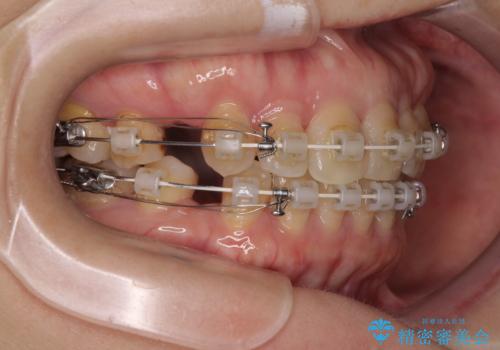

- 矯正装置

- 審美装置

- 前歯のデコボコと口元の突出感を気にして来院された患者様です。

上下前歯がくちばしのように突出していたため、上下左右の第一小臼歯4本を抜歯し、ワイヤー装置にて矯正治療を行うこととしました。

上顎骨に対して下顎骨がやや前方位に位置しているため、歯肉退縮を回避するために下顎前歯をあまり内側に移動させることができない状況でしたが、十分に口元の突出感を改善することができました。